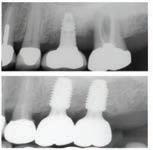

Christopher Chung, DMD

Smile Again Dental Group 818-776-9300

์ž„ํ”Œ๋ž€ํŠธ ํ™˜์ž : ์ผ๋ฐ˜ ์นซ์†” + ์น˜๊ฐ„ ์นซ์†”, ์›Œํ„ฐํ”ฝ ๋ณ‘ํ–‰ ์‹œ ์„ธ์ • ํšจ๊ณผ๊ฐ€ ํƒ์›”.